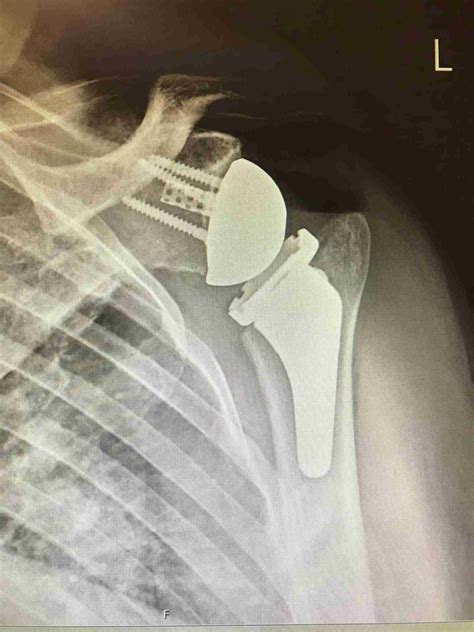

Shoulder replacement surgery, also medically referred to as shoulder arthroplasty, is a surgical intervention where the damaged parts of the shoulder joint are removed and replaced with artificial components, known as prostheses. The shoulder is a ball-and-socket joint, and when the smooth cartilage that allows the bones to glide against each other wears away, the result is painful bone-on-bone contact.

During the procedure, an orthopedic surgeon replaces the humeral head (the ball) with a metal ball and replaces the glenoid (the socket) with a smooth plastic cup. The goal is to eliminate pain and allow the patient to return to normal functioning with a stable and comfortable joint.